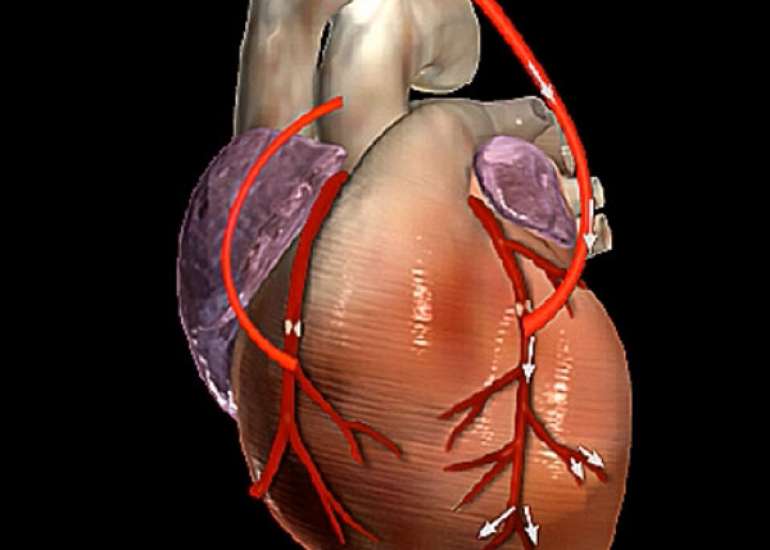

Dr. Yadava completed his medical graduation and Masters in Surgery from Maulana Azad Medical College and had joined Armed Forces as a Surgical Specialist. He cleared his DNB Examination in General Surgery in the year 1983 and completed his training in cardiothoracic surgery at the Cardio Thoracic Center, Armed Forces Medical College, Pune in 1985. For advanced training, went to Australia and worked under and along with some of the greatest cardiac surgeons of recent times. Besides adult cardiac surgery, he was also trained in Paediatric Cardiac Surgery in Melbourne & Japan and successfully cleared the National Boards in Cardiothoracic Surgery (DNBE). He was honoured with Membership of the National Academy of Medical Sciences (MNAMS) in 1994; FICC in 2003, FIACS in 2005 & FCSI in 2012. He has as an experience of over 12,000 open heart surgical procedures and his special field of interest is coronary artery bypass surgery especially total arterial revascularisation & beating heart surgeries (Minimally Invasive).